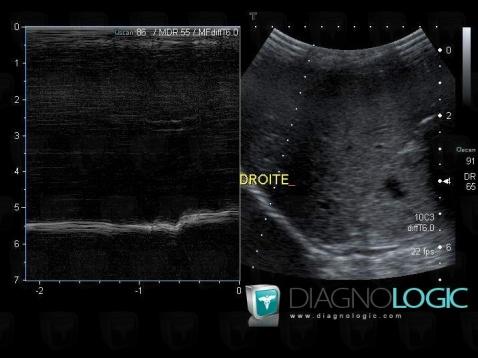

Paralysie-nerf phrénique, Diaphragme, Echographie

Voici les informations spécifiques à l'image clé ci dessus:

- Diagnostic Paralysie du nerf phrénique, Localisation(s) Diaphragme, comportant les gammes